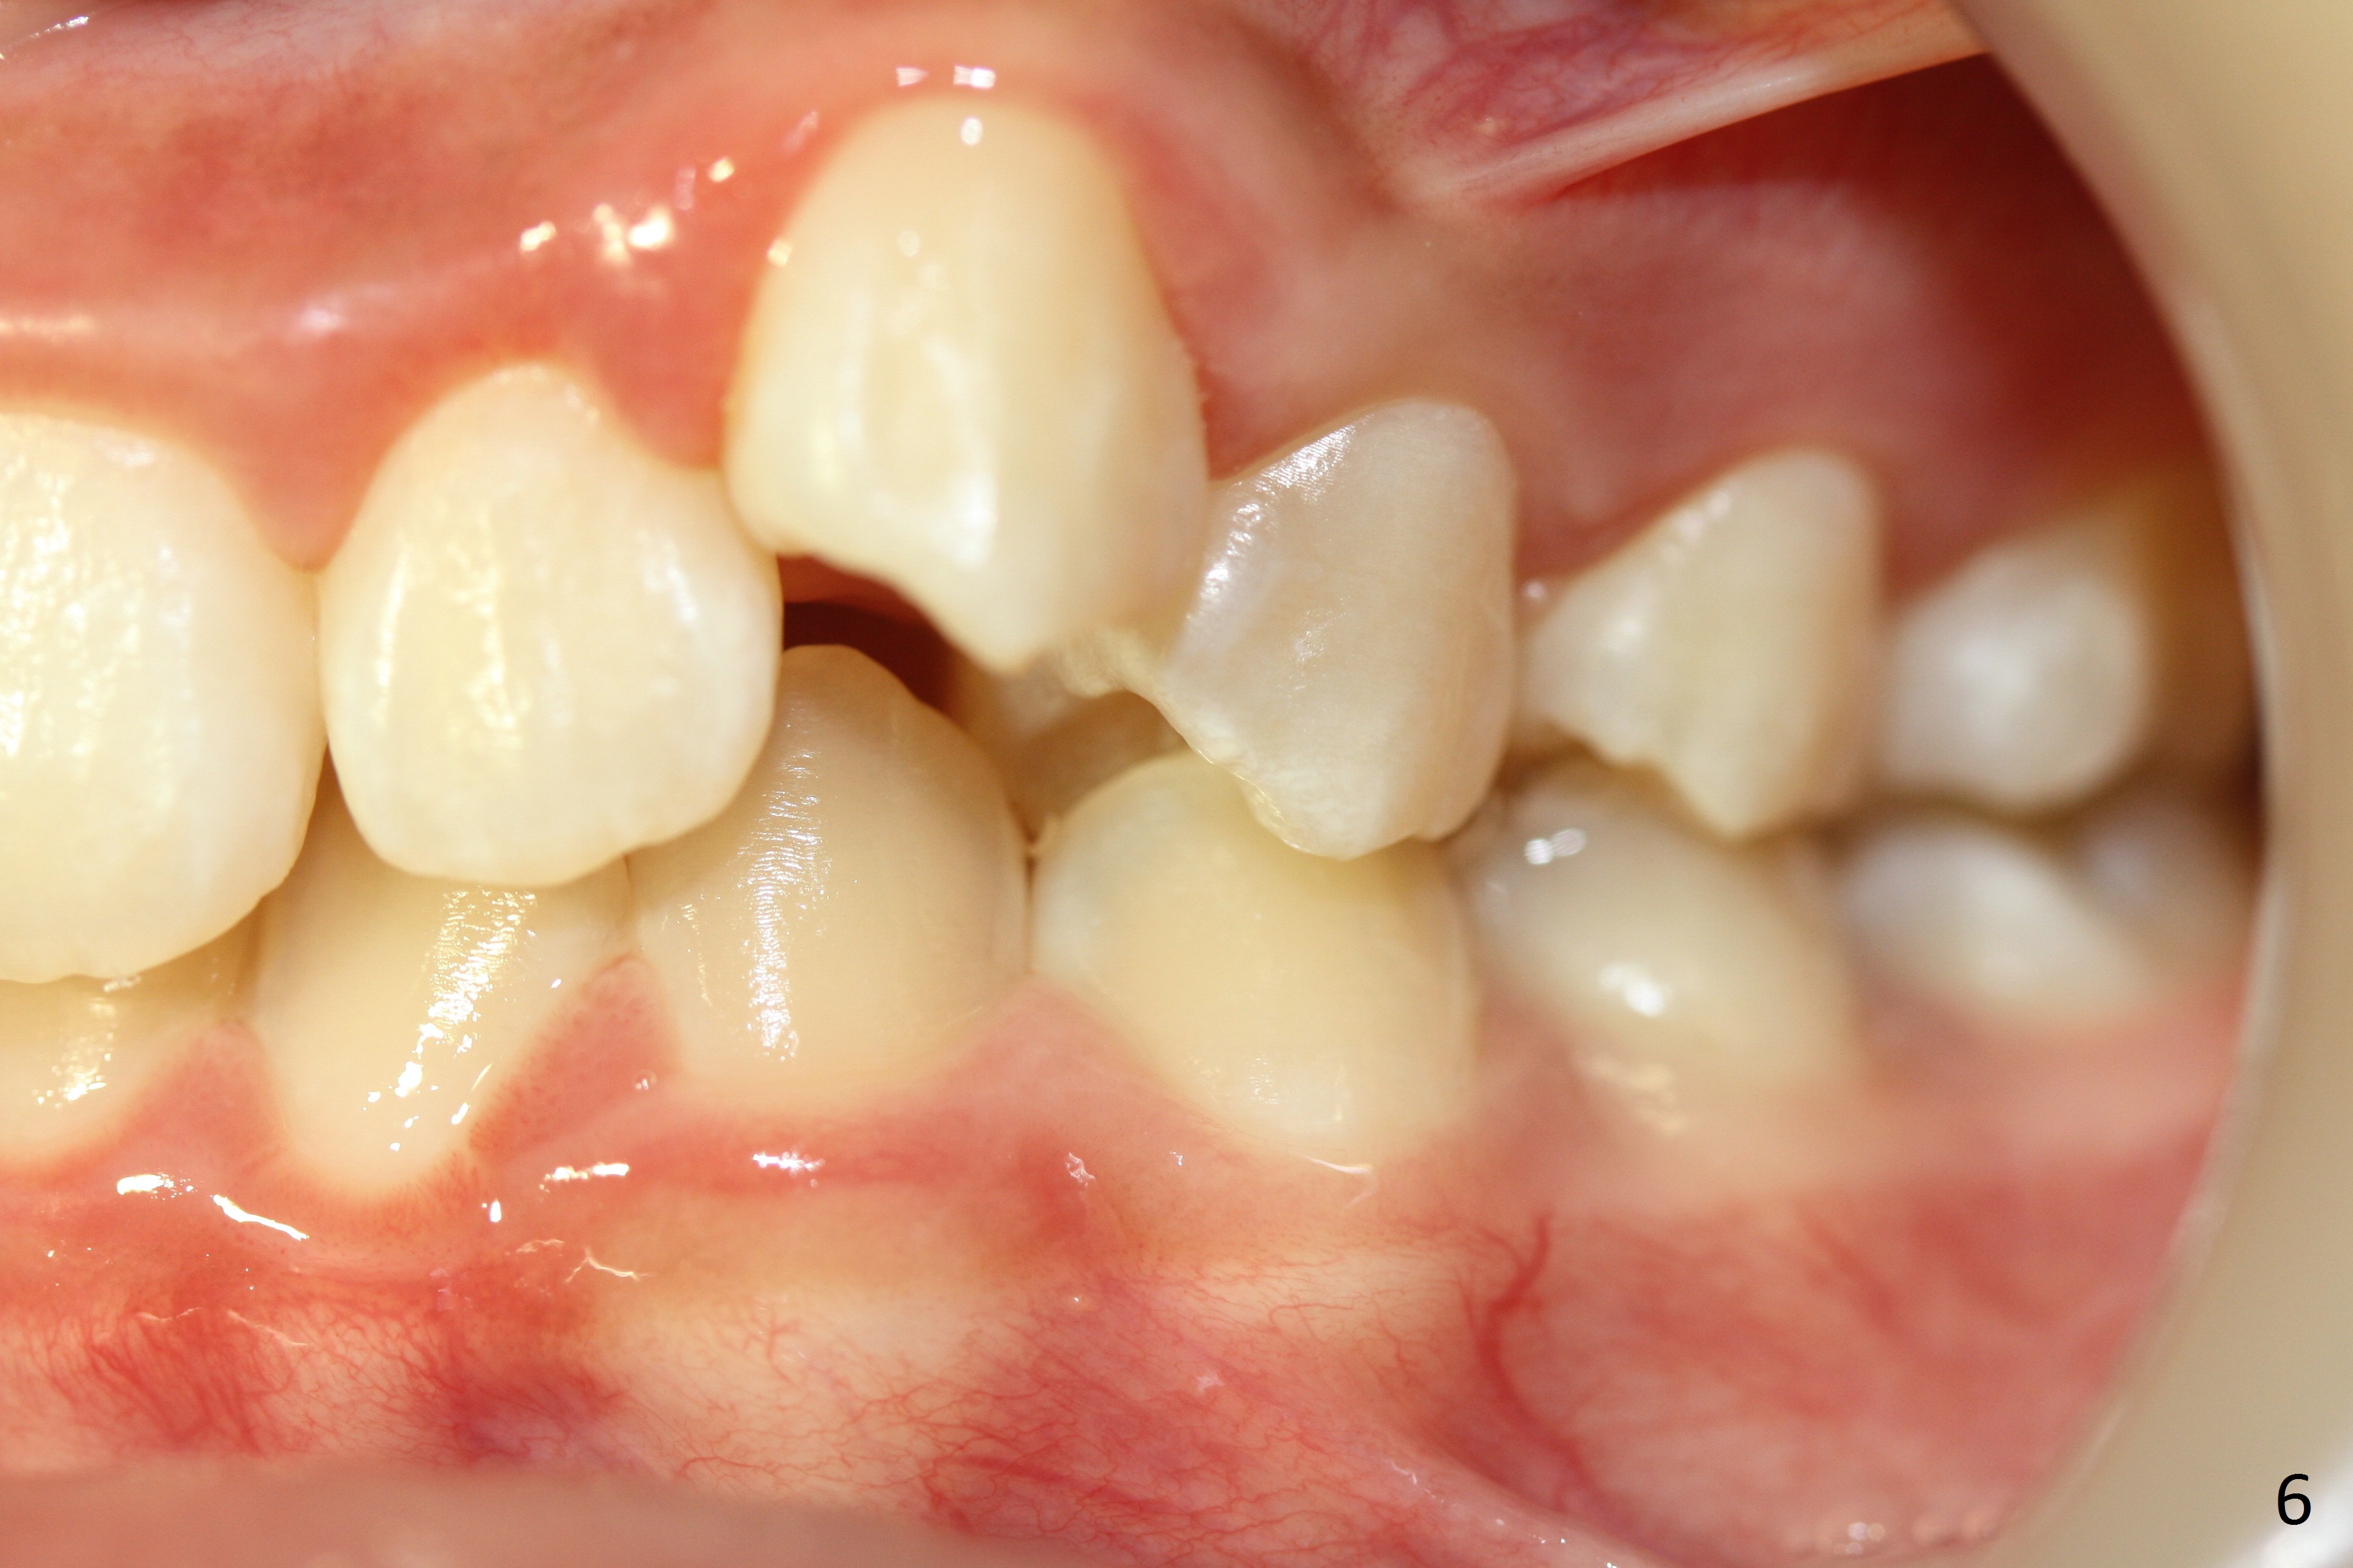

A 12-year-old girl has Class II Division I malocclusion (Fig.5,6) with protrusion of the upper lip (Fig.3). With extraction of the upper 1st bicuspids, postop facial profile improves (Fig.3', 4').

Retract the cheek retractor as posterior as possible when taking the lateral occlusal view (Fig.6,6'). Show interdigitation. Take a few of straight shots in addition to slanted ones (Fig.6).